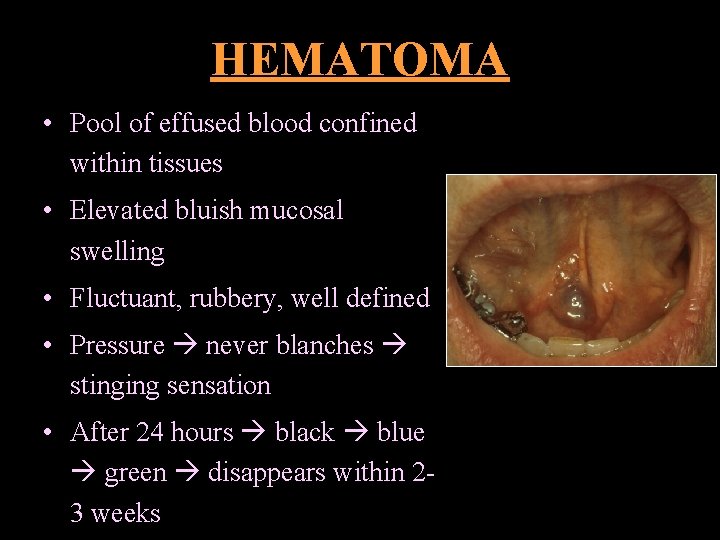

HEMATOMA • Pool of effused blood confined within tissues • Elevated bluish mucosal swelling • Fluctuant, rubbery, well defined • Pressure never blanches stinging sensation • After 24 hours black blue green disappears within 23 weeks